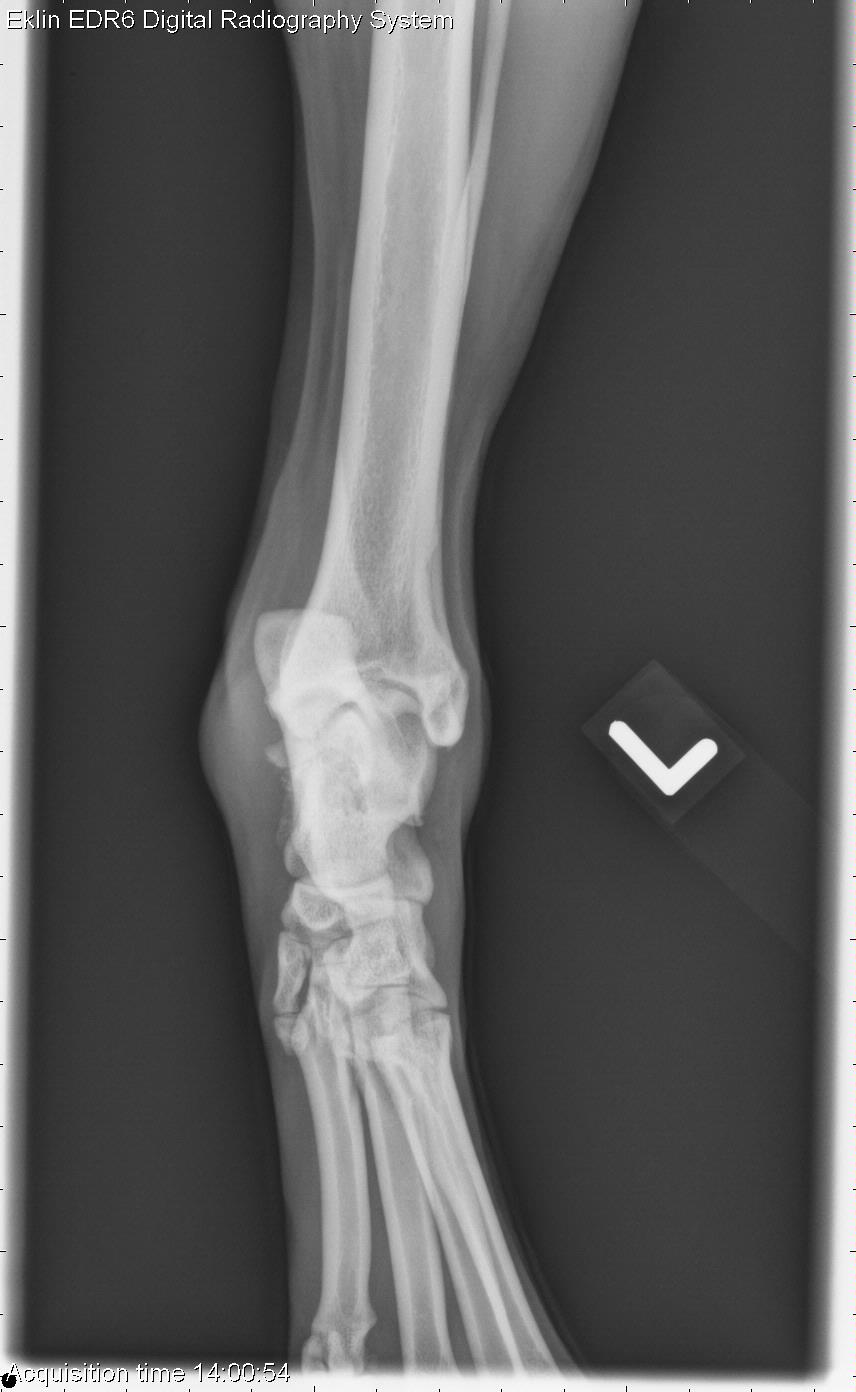

Today’s case is a 7-year-old male neutered Labrador retriever. Owner noticed a lump on his left hock about 5 days ago. What are your findings?

There is a thin, radiolucent fracture line present in an oblique orientation on the proximal talus. This is best seen on the caudocranial projection. There is new bone proliferation on the medial and lateral aspects of the talus near the fracture margin. There is increased soft tissue opacity at the level of the tarsocrural joint indicating effusion. On stressed projections, the medial tibiotarsal joint is slightly widened. The arrows indicate the direction of stress applied to the joint.

Note – was not a true fracture.

Chronic, non displaced fracture of the left talus with marked tarsocrural effusion and osteoarthrosis. Mild joint instability may indicate disruption of the medial collateral ligaments.